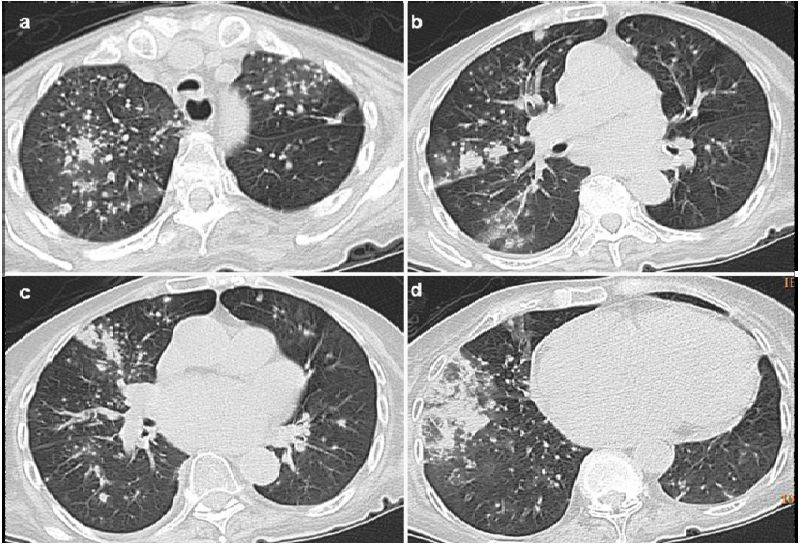

胸部X光片和CT扫描显示(图:1,2,3,4,5,6,7):

1、肺部空腔,包含坚实的圆形物质,通过空气边缘与墙壁分开。此功能称为“空气新月”标志。

2、另一个常见特征是腔壁和邻近胸膜增厚。

3、这种真菌球可能是移动的。

图3:轴向CT显示55岁女性的曲霉病患者发现空气新月形上叶与固结区域相关,周围有磨玻璃样改变。

图4:轴位CT显示右下叶的团块,中央区域为空洞,考虑诊断为曲霉菌,术后诊断为肺癌。

图7:轴向和冠状CT扫描显示空腔内的真菌球,与支气管扩张和多发小叶中央结节相关。